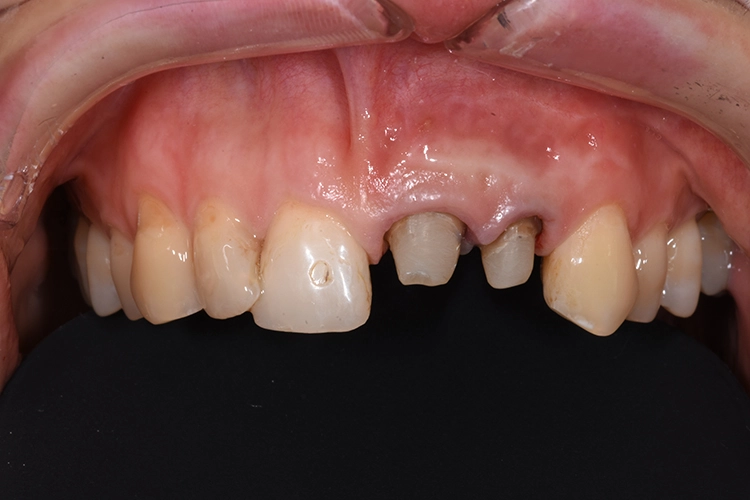

Fall 2: KFO-Extrusion

Ihr wurden die verschiedenen Behandlungsmöglichkeiten erklärt. Die Patientin wünschte sich den Erhalt der eigenen Zähne. Aufgrund der Breite der Lücke und schwierig zu schienender Situation entschieden wir uns für eine kieferorthopädische Extrusion der beiden Wurzelreste.

Dr. Blume